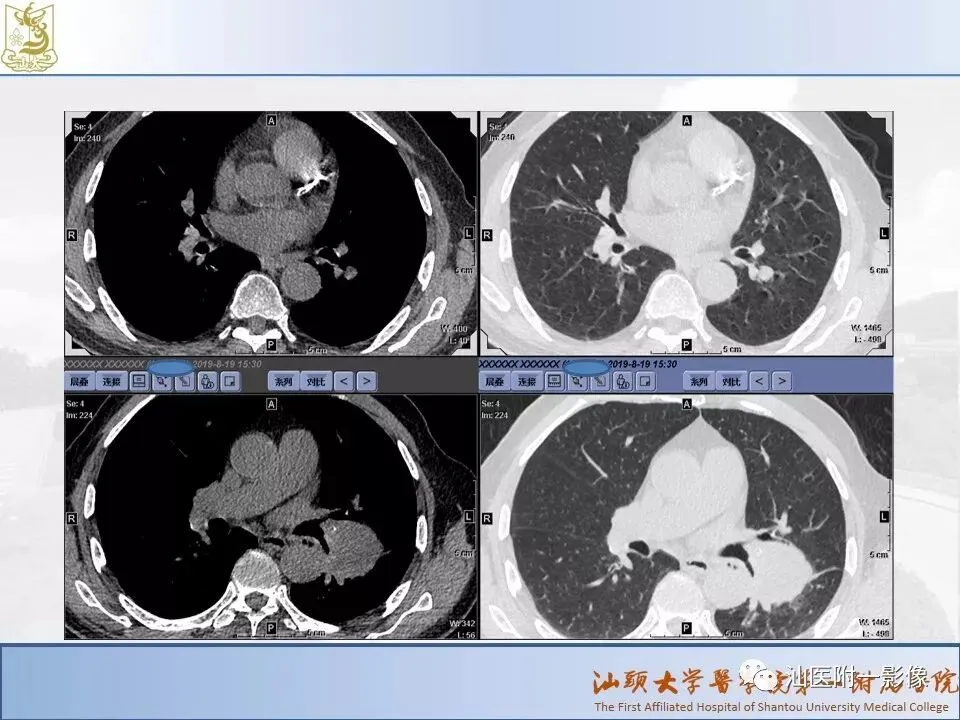

肺结节分类、处理及浅识肺结节分类影像报告和数据系统(Lung-RADS)

来源:汕医附一影像

说明:本课程病例主要来源于本院病例及参考资料,

无涉及病人隐私,仅做教学用途。